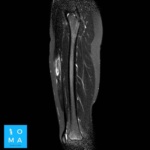

🔹Varón de 12 años que consulta por tumefacción en región anterior de muslo derecho. Refiere molestia a ese nivel 3 días antes, después de pique en partido de fútbol.

🔹Cambios inflamatorios asociado a edema y banda líquida que rodea a la unión miotendinosa central del sector medio del músculo recto anterior del cuádriceps derecho, de 10 mm de extensión, evocador de desgarro de la unión miotendinosa grado II.

🔹En un segundo tiempo se realiza ecografía dirigida, confirmando los hallazgos a nivel del tendón central del músculo recto

anterior del cuádriceps derecho, presentando desgarro grado II, asociado a un

aumento del flujo vascular al examen Power doppler.